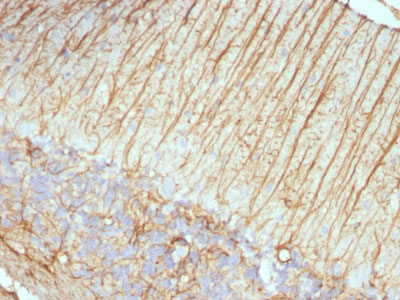

Formalin-fixed, paraffin-embedded human Schwanoma stained with GFAP Monoclonal Antibody (ASTRO/789).

Formalin-fixed, paraffin-embedded human Cerebellum stained with GFAP Monoclonal Antibody (ASTRO/789).

Formalin-fixed, paraffin-embedded Rat Cerebellum stained with GFAP Monoclonal Antibody (ASTRO/789). |

This MAb recognizes a protein of ~50kDa which is identified as Glial Fibrillary Acidic Protein (GFAP). It shows no cross-reaction with other intermediate filament proteins. GFAP is specifically found in astroglia. GFAP is a very popular marker for localizing benign astrocyte and neoplastic cells of glial origin in the central nervous system. Antibody to GFAP is useful in differentiating primary gliomas from metastatic lesions in the brain and for documenting astrocytic differentiation in tumors outside the CNS.

GFAP, a class-III intermediate filament, is a cell- specific marker that, during the development of the central nervous system, distinguishes astrocytes from other glial cells.